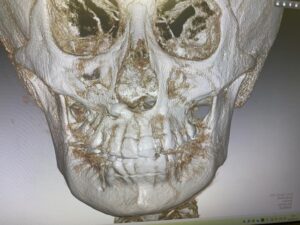

④ CTスキャン(ケースにより未撮影の場合あり)

⑤ その他、必要に応じCTスキャンを利用した気道分析

(👆 当院設置のCTスキャン画像)